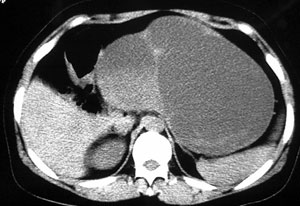

强化片

这个要问下病史,如无胰腺炎病史首先考虑胰腺体尾部的粘液囊腺瘤,此瘤太大,有分叶和实性成份要考虑恶性或潜在恶性可能,后两幅主动脉左旁结节状强化影止于左肾静脉,考虑双下腔静脉,请结合往下的片

胰腺体尾部囊实性占位,境界清晰,内有间隔呈多房性,周围无炎性改变,考虑胰腺囊腺瘤。

胰腺体尾部囊实性占位,有分隔.内无脂肪及钙化等组织.考虑:胰腺囊腺瘤可能性大, 囊腺癌不除外 ;

患者过去有无胰腺炎的病史,还要考虑到假性囊肿。

以下是引用守望可可西里在2006-8-30 10:57:00的发言:[br][br] 定位:胰腺体尾部。[br] 定性:胰腺囊腺癌可能性大。[br] 理由:胰腺体尾部呈多囊状分叶,部分病灶与前腹壁粘连,且下部形态不规则,毛糙不整、凸凹不平。囊壁厚薄不一致,多个大小不等壁结节突入,囊壁及壁结节明显不均匀强化。偏右侧囊内见液-液平面样相对高密度,呈与壁结节类似强化。性质:1.出血?2.壁结节?

以下是引用duguo在2006-8-30 12:13:00的发言:[br]支持胰腺囊腺癌诊断,建议穿刺活检.